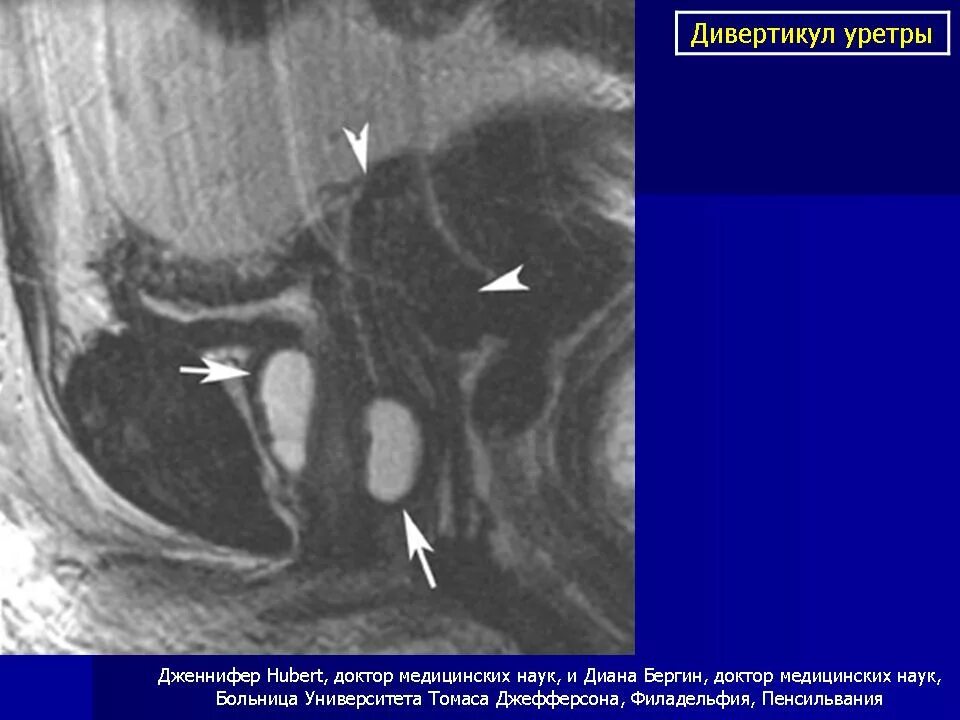

Дивертикул мочевого пузыря что это такое